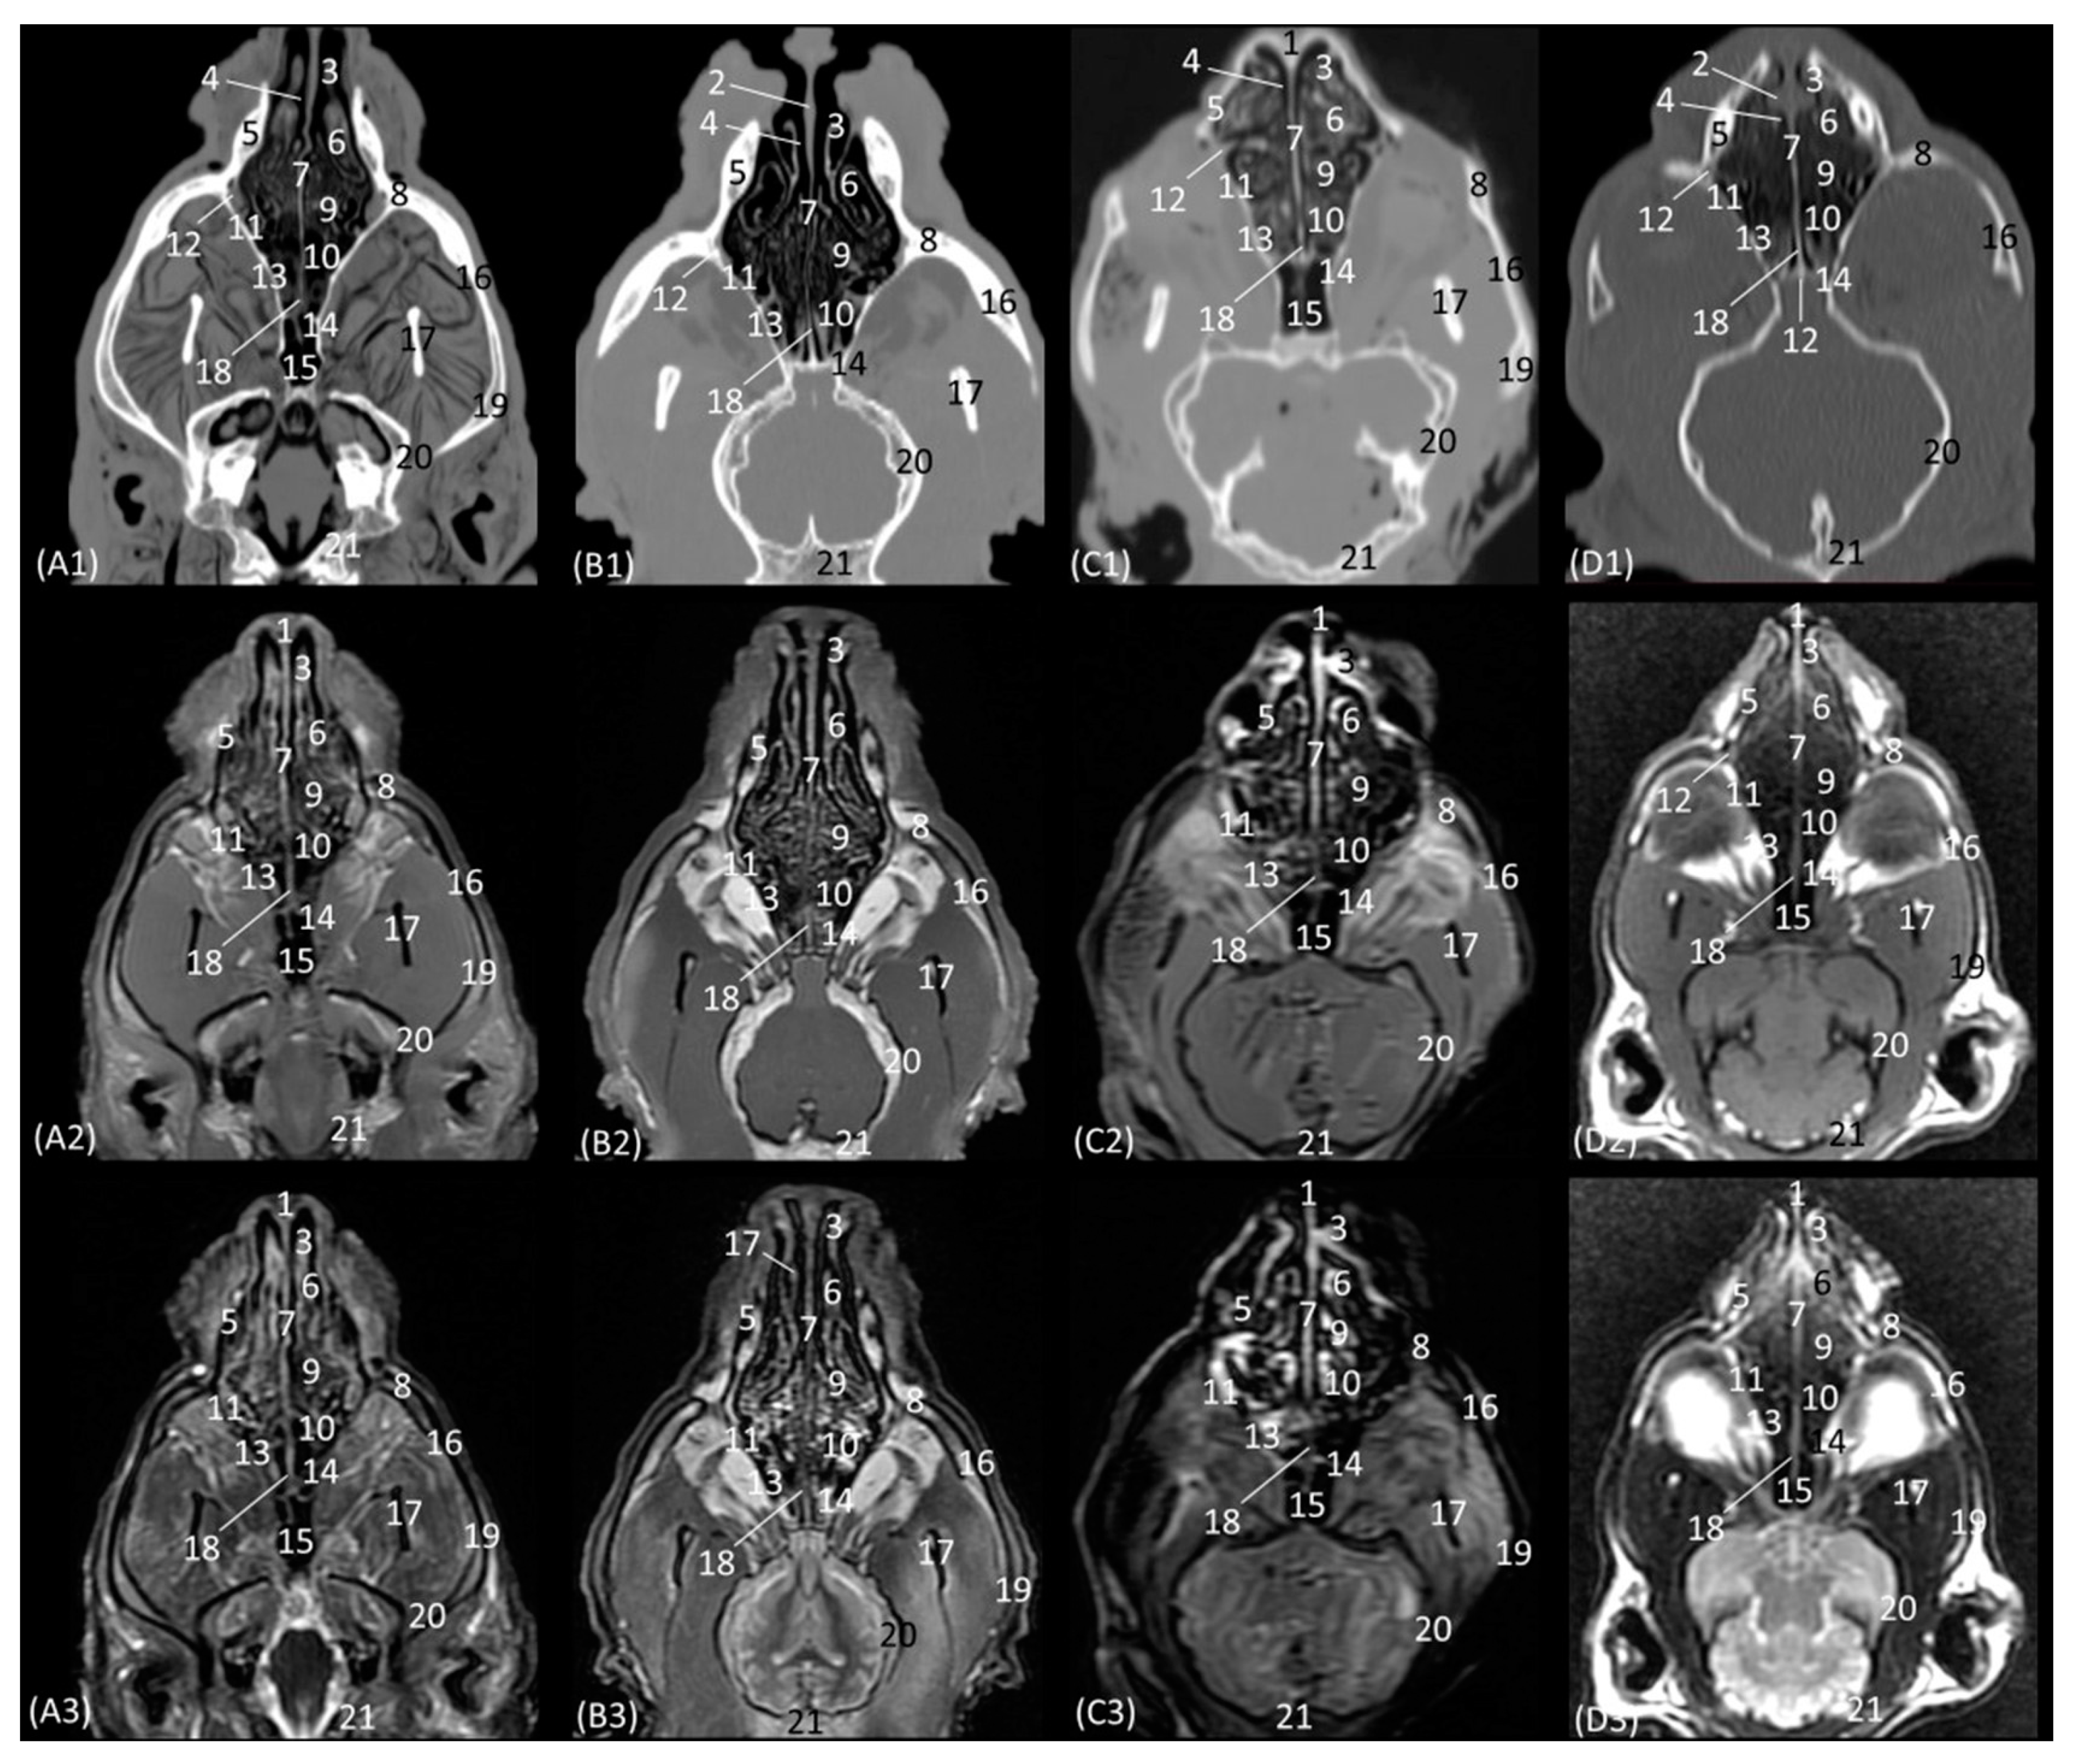

Figure 16A–C represent a more caudal view at the level of the ethmoidal labyrinth. Only views of the lion, cheetah, and cat are included, as due to the rigidity of the fixed structures of the nasal cavity of the leopard, access by rhinoscopy for a more caudal study of the nasal cavity is presented. In this section, the third and fourth endoturbinates were identified, as well as the opening of the sphenoid sinus, which is close to the floor of the nasal cavity. In the cat, the nasopharyngeal or choanal opening can also be identified ventrally, and in the cheetah, the pharyngeal orifice of the auditory tube can be identified on the lateral wall of the nasal cavity, ventral to the third and fourth endoturbinates.

Figure 16. Endoscopic images of the nasal cavity at the level of the ethmoidal labyrinth. The level of this endoscopic study is shown above in the sagittal anatomical section. Images are observed so that the right side of the head is to the left of the image. (A): Lion; (B): cheetah; and (C): cat. 1. Ventral nasal concha; 2. 4th endoturbinate; 3. 3rd endoturbinate; 4. opening of the sphenoidal sinus; 5. ventral nasal meatus; 6. nasal septum; 7. nasal cavity: lateral wall; 8. lateral nasal gland; 9. choana; 10. pharyngeal orifice of the auditory tube.

The pharyngeal orifice of the auditory tube can be identified in more detail in Figure 17C, located on the lateral wall. The leopard is the only species where the orifice of the lateral nasal gland was identified, being located close to the straight fold and, more specifically, in the oblique fold (Figure 17A).

Figure 17. Endoscopic images of the nasal cavity showing the aperture of the lateral nasal gland duct, frontal opening, and pharyngeal orifice of the auditory tube (observed only in big cats). The levels of this endoscopic study are shown above in the sagittal anatomical sections. Images are observed so that the right side of the head is to the left of the image. (A): Leopard; (B): lion; and (C): cheetah. 1. Nasal septum; 2. nasal cavity: lateral wall; 3. pharyngeal orifice of the auditory tube; 4. straight fold; 5. dorsal nasal meatus; 6. dorsal nasal concha; 7. frontal opening; 8. nasal cavity: roof; 9. alar fold; 10. ventral nasal concha; 11. nasal cavity: floor; 12. oblique fold; 13. aperture of the lateral nasal gland duct.

Below, Figure 18A–C detail the nasopharyngeal or choanal opening in the lion, cheetah, and cat on the floor of the nasal cavity, showing the soft palate at this level. In this view, we can also see the pharyngeal opening of the auditory tube on the lateral wall of the nasal cavity.

Figure 18. Endoscopic images at the level of the choana and nasopharynx. The level of this endoscopic study is shown above in the sagittal anatomical section. Images are observed so that the right side of the head is to the left of the image. (A): Lion; (B): cheetah; and (C): cat. 1. Presphenoid bone; 2. nasal septum; 3. nasal cavity: lateral wall; 4. choana; 5. nasal cavity: floor; 6. pharyngeal orifice of the auditory tube; 7. soft palate; 8. palatine aponeurosis.